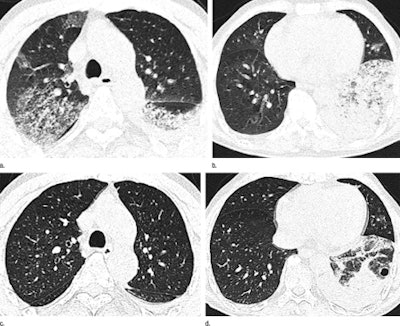

In scans of the 12 infected patients in the study, the most common findings were ground-glass opacities (GGOs), consolidation, air bronchograms, and interlobular septal thickening, with the severity of these features mirroring the severity of the illness at presentation and throughout follow-up, wrote the authors from Shanghai Medical College of Fudan University (Radiology, July 2, 2013).

At CT, all patients had lung lesions affecting three or more lobes with a bilateral distribution, but patients were usually affected more on one side than the other, the group reported. The right lung was more affected in seven patients and the left lung in three, with roughly equal distribution in two patients. Extensive GGOs were the most prominent feature, seen in all 12 patients, though some individual lobules were unaffected.

Additional findings included consolidations, bronchograms, and interlobular septal thickening (each in 11 patients). Less common were centrilobular nodules (seven patients), cystic changes (four patients), and bronchial dilatation and subpleural linear opacities (each in three patients), Wang and colleagues wrote.

Rapidly progressing GGOs and consolidations with air bronchograms and interlobular septal thickening, all with a right lower lobe predominance, are the main imaging findings seen with H7N9 pneumonia, the authors concluded. The severity of these findings corresponded to disease severity at presentation.